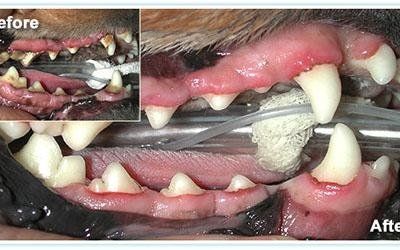

La malattia dentale ha dimostrato di essere un fattore importante che contribuisce a molti gravi problemi di salute, tra cui problemi di fegato, reni e le malattie cardiache. Gli studi dimostrano che gli animali domestici con "bocche sane" hanno meno problemi di salute e la vita di qualità più lunga di quelli animali domestici con malattia dentale severa.

La malattia parodontale è un'infiammazione dei tessuti moli circostanti dei denti e in fase avanzata forma la placca prodotta da batteri, tartaro calcificato. Nelle fasi finali della malattia parodontale, i tessuti circostanti del dente sono danneggiati, l'osso erode e il dente si allenta che è estremamente doloroso e scomodo per animale.Cattive condizioni di salute dentale può portare alla diminuzione dell'appetito, mancanza di energia, cattivo odore dalla bocca.

Le statistiche ci dicono che oltre 70 % dei gatti e oltre 80 % dei cani sono affetti delle patologie dentarie e gengivali già dell’età di tre anni. Medico specializzato in odontostomatologia veterinaria che dispone di attrezzatura dedicata si occupa di tutti problemi che provoca la malattia dentale:ablazione del tartaro,estrazione dei denti malati,fratturati ,denti da latte o estrazione di tutti i denti nel caso di stomatite ulcerativa nel gatto,cure endodontali.